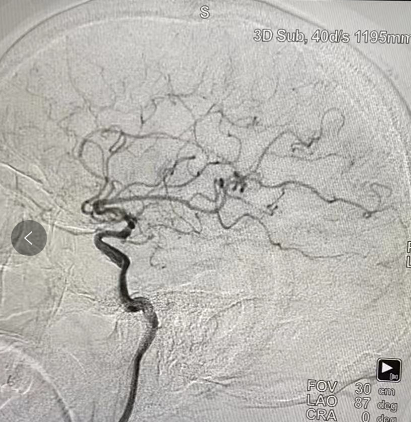

苗树船老师在为该患者造影的同时中再次耐心详细地讲解了造影的准备程序、操作步骤和术后处理事项,并对医生们提出的问题详细解答。在苗老师细心精细的操作下,州人民医院神经外科完成了首例减影血管造影,自此阿坝州神经外科医学迈开了由外科手术转向介入治疗的第一步,为下一步介入治疗技术的开展奠定了坚实基础。

在首例减影血管造影技术成功开展后,苗树船老师继续指导州人民医院神经外科开展脑血管造影检查,使部分患者在CT和MRI检查结果存在争议的情况下,利用减影血管造影技术在血管方面呈现的优势,及时明确了患者病因,为后续的治疗指明了方向。该项技术在州人民医院开展为患者提供了方便,患者不再需要转到上级医院行该项检查,为患者节约了时间和费用。